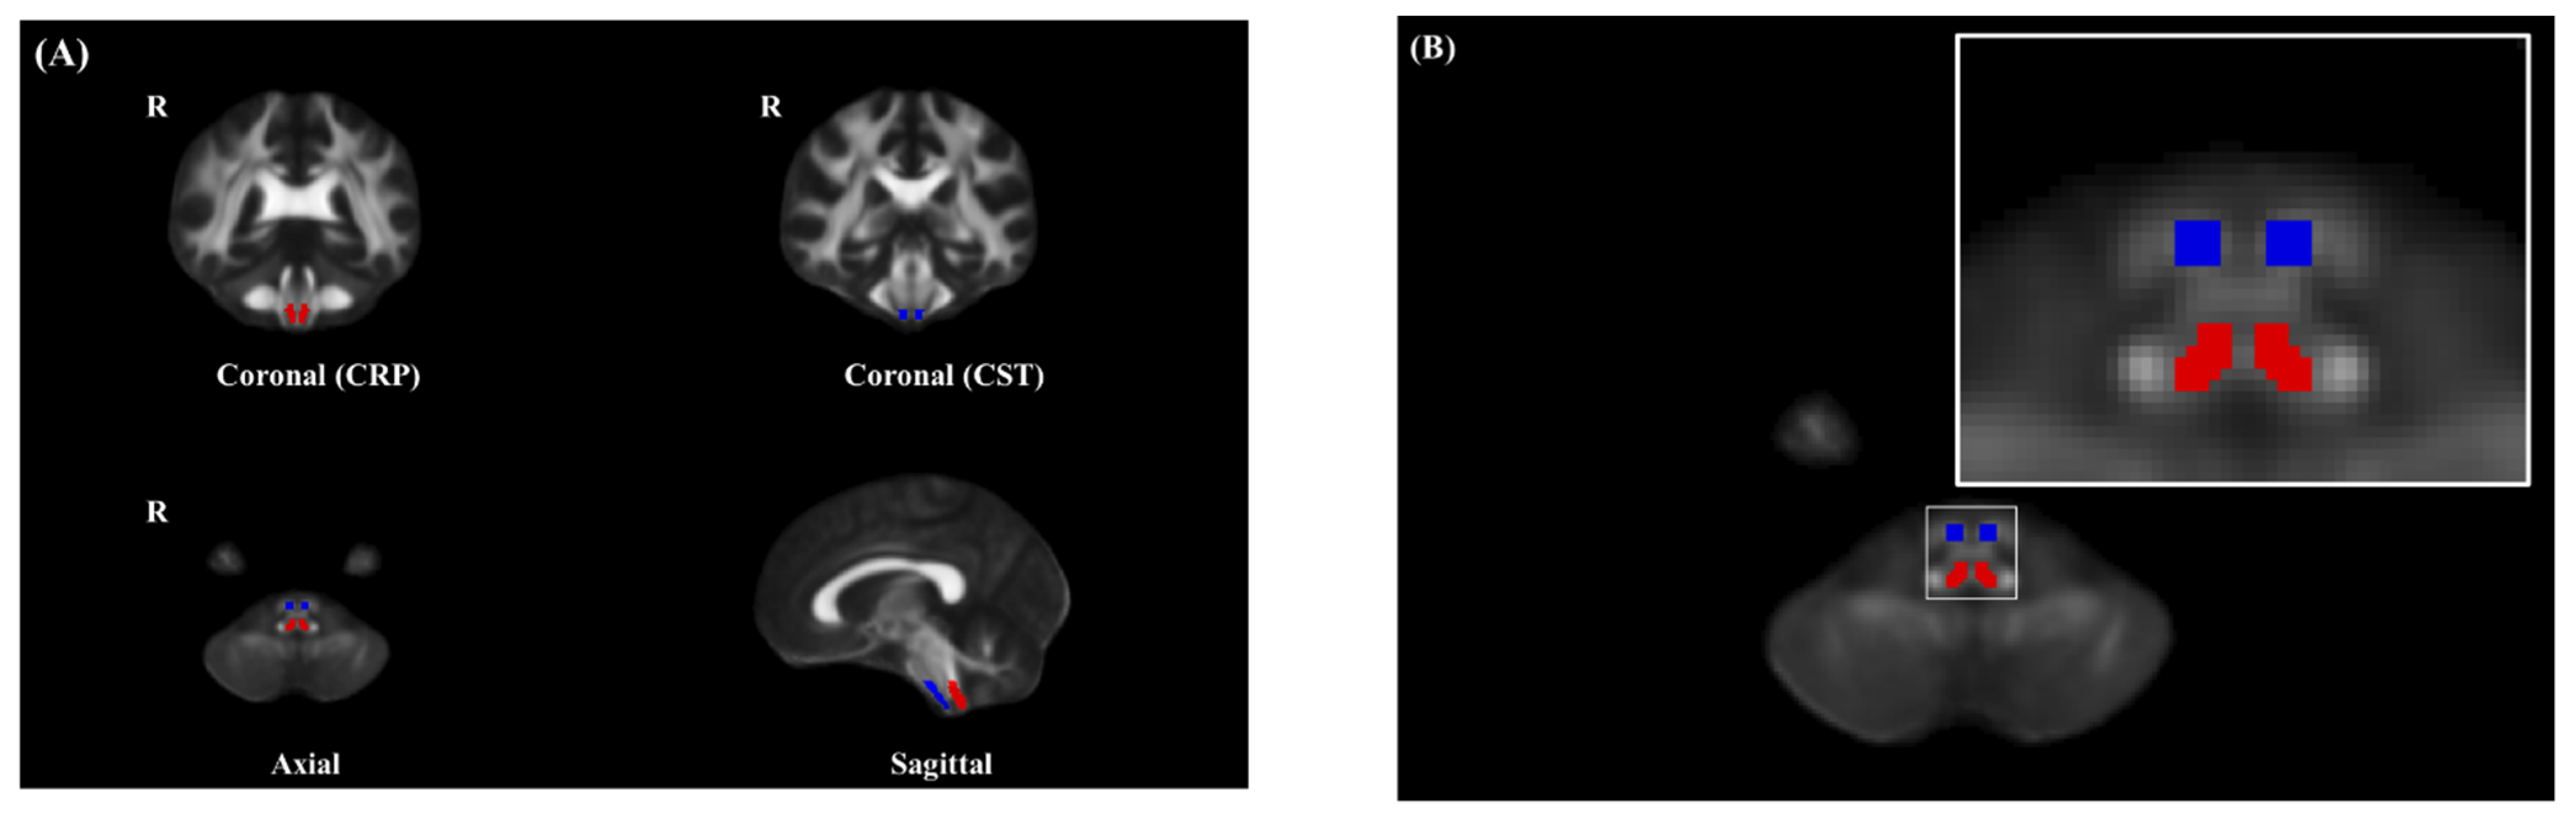

3.3. ROI Analysis of FA of the CST in the Brain Stem

3.4. ROI Analysis of FA of the CRP in the Brain Stem